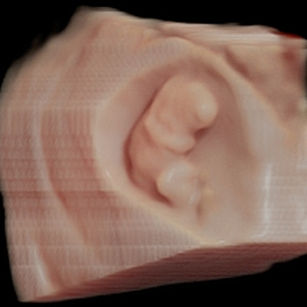

9 Weeks Pregnant

Size: ~0.9 inch (2.3 cm), the size of a Grape!

Development Highlights:

Limbs grow longer; elbows and knees visible.

Tooth buds appear under gums.

Eyes more developed, but eyelids remain fused.

Brain continues rapid development; nervous system forming connections.